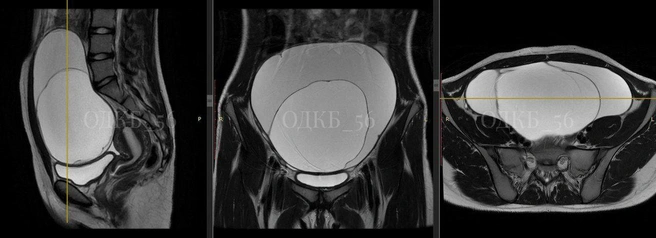

В руках медиков оказалась 14-летняя девочка, которая обратилась в экстренное приёмное отделение с сильными болями в животе — и он даже вздулся. После УЗИ и МРТ органов малого таза стало ясно, что без операции не обойтись — обнаружено объемное образование больших размеров (диаметр — 20 сантиметров). И хирурги подозревали, что это образование — злокачественное.

— Ребенок был консультирован детским онкологом, совместными силами была выбрана тактика хирургического лечения. Учитывая риски, командой хирургов детского хирургического отделения № 1 в срочном порядке было выполнено оперативное лечение. Образование, исходящее из правых придатков матки, размером 20 сантиметров в диаметре, было удалено в полном объеме, хотя было сложно, из-за выраженных спаечных процессов в малом тазу, — рассказала главный внештатный детский гинеколог МЗ Оренбургской области Аниса Гарайс.